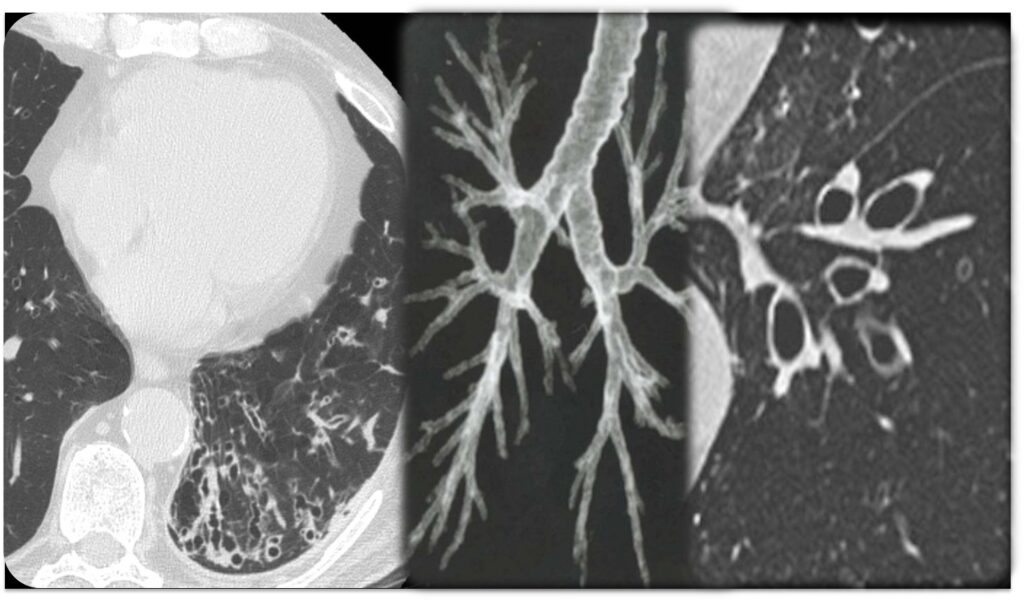

Nodulo Polmonare

Il nodulo polmonare è un’opacità di dimensione < 3 cm, che non coinvolge la pleura, ed in genere non è associato a linfoadenopatia. L’eziologia del